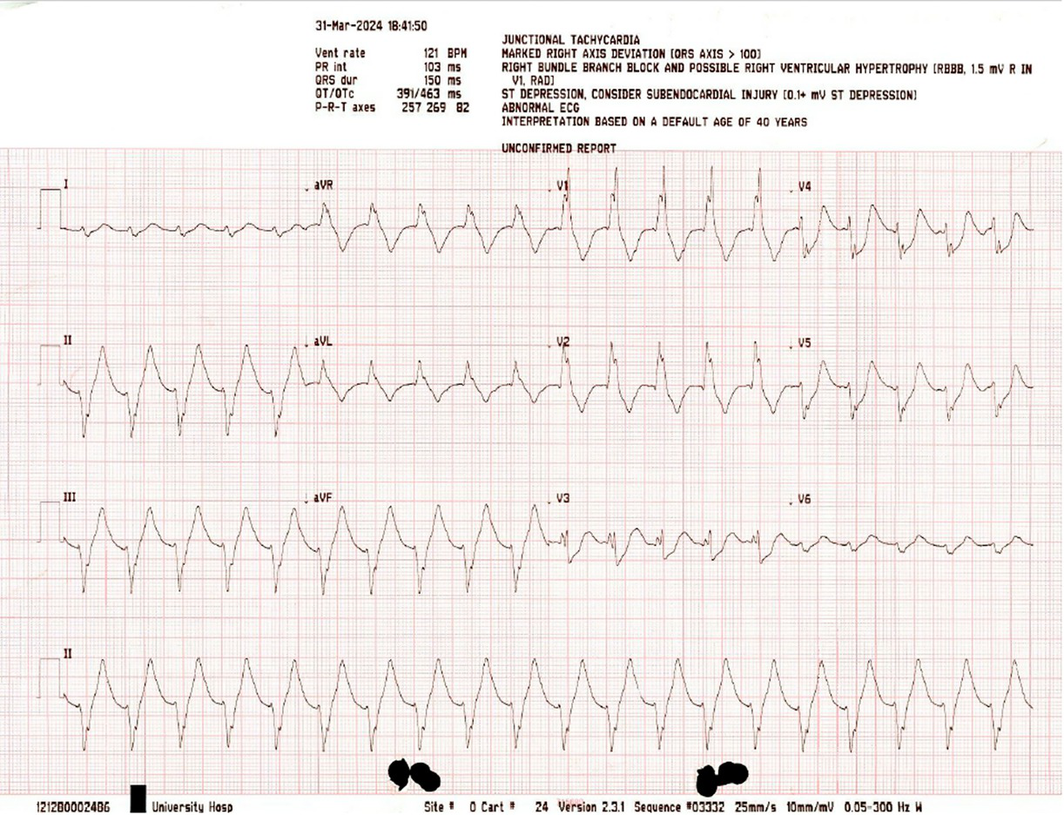

The patient underwent 19 minutes of cardiopulmonary resuscitation (CPR), including four defibrillator shocks of 200 J for ventricular fibrillation (Box 1) and pulseless ventricular tachycardia before return of spontaneous circulation (RoSC) of a broad complex tachycardia with palpable pulse (Box 2).